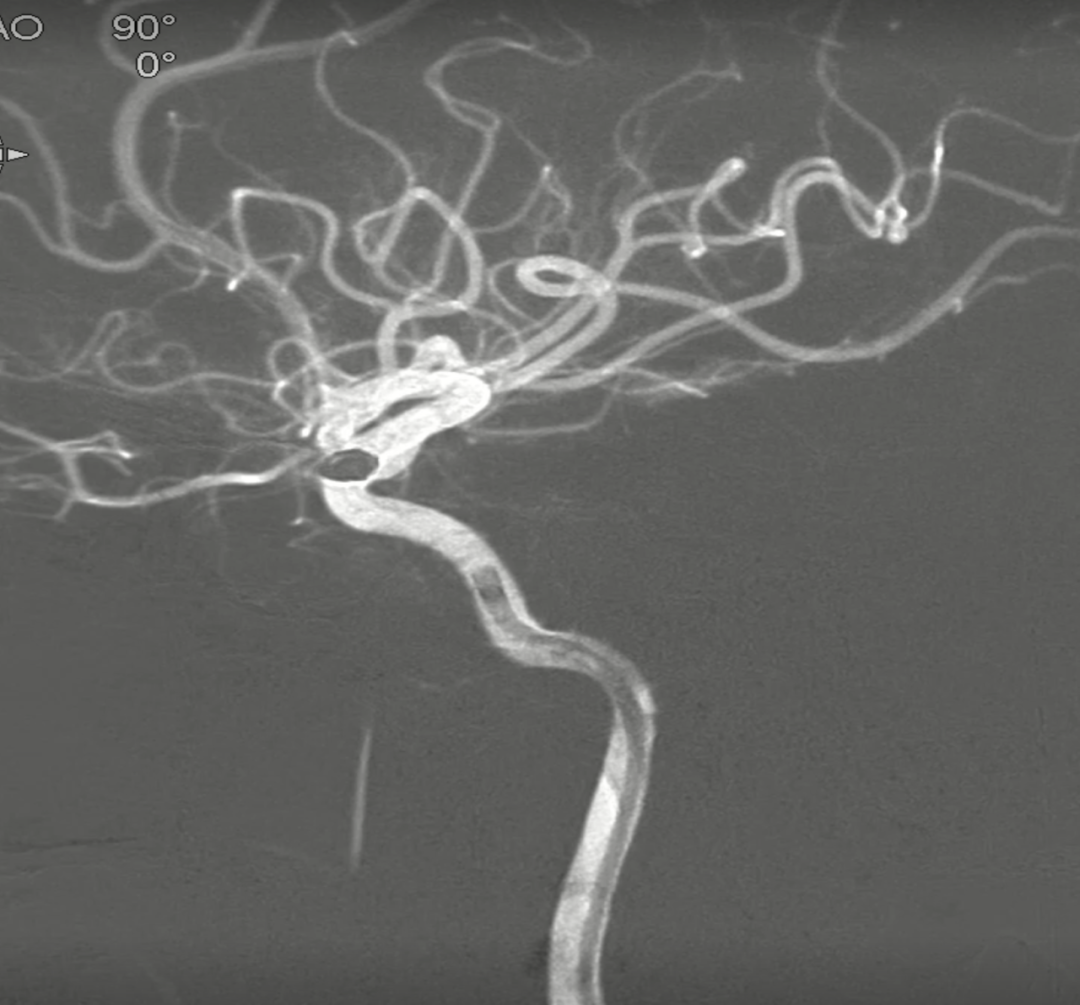

术后正侧位造影:Raymond Ⅲ级

术后支架重建:支架打开良好,近端Marker位于颈内动脉分叉处

继续填入Target 1.5/2弹簧圈成篮,后完全释放支架,其近端位于颈内动脉分叉处,远端位于A1远端。